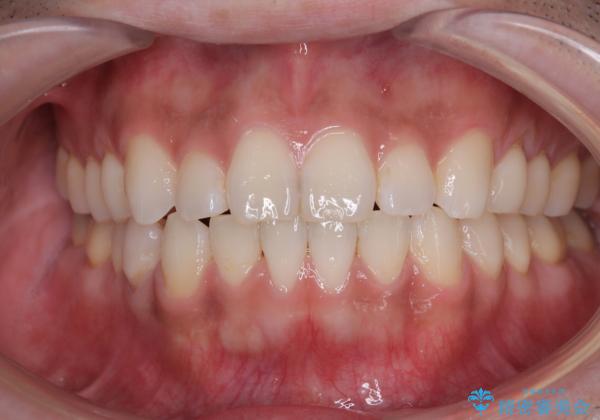

一年と数か月で矯正を終えることができました。

下顎前歯部には後戻り防止のワイヤーを装着しています。

目立たない装置でデコボコを改善 ハーフリンガルによる矯正治療